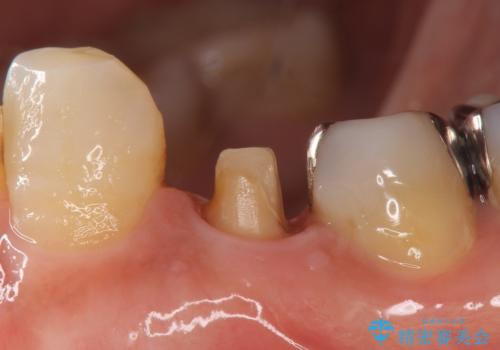

- 他院にて左下4の根管治療を行っていたが、疼くような痛みが引かないため当院にいらっしゃった方の症例です。

左下4の再根管治療を行い症状が治まったのち、オールセラミッククラウンによる補綴を行いました。